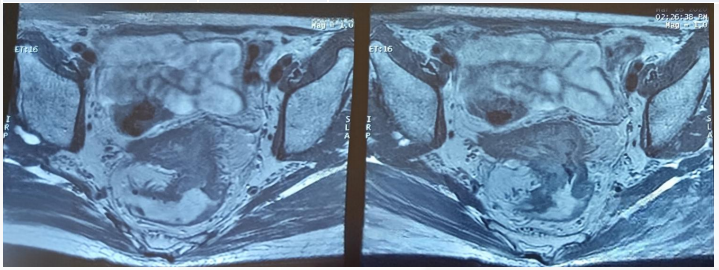

胸腹CT提示肝脏多发转移、双肺结节转移,腹腔淋巴结肿大(图2)。

盆腔MRI提示直肠癌(病变累及范围约10.6cm)(图3)。

图2. 胸腹部CT检查

图3. 盆腔MRI检查